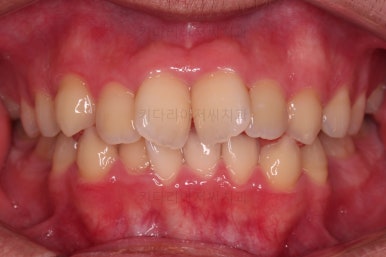

초진 시, 입안의 모습입니다.

치아를 모두 담기에 골격이 매우 작았어요.

이런 경우 치열이 ㅃ뚤어지거나 입이 튀어나오거나 뻐드렁니가 되거나 특정 치아가 묻혀버리거나 맨 뒤치아가 마치 사랑니처럼 올라오지 못한다거나 등등의 문제가 생기는데요.

이번 환자분은 전반적으로 삐뚠 상황이었어요.

앞니도 대칭적으로 삐뚤어져 흔히 나비치아라고 하는 형태로 보이고, 아랫니들은 U자 아치의 형태가 찌그러져 있네요.

당연히 교합도 맞지 않고요.